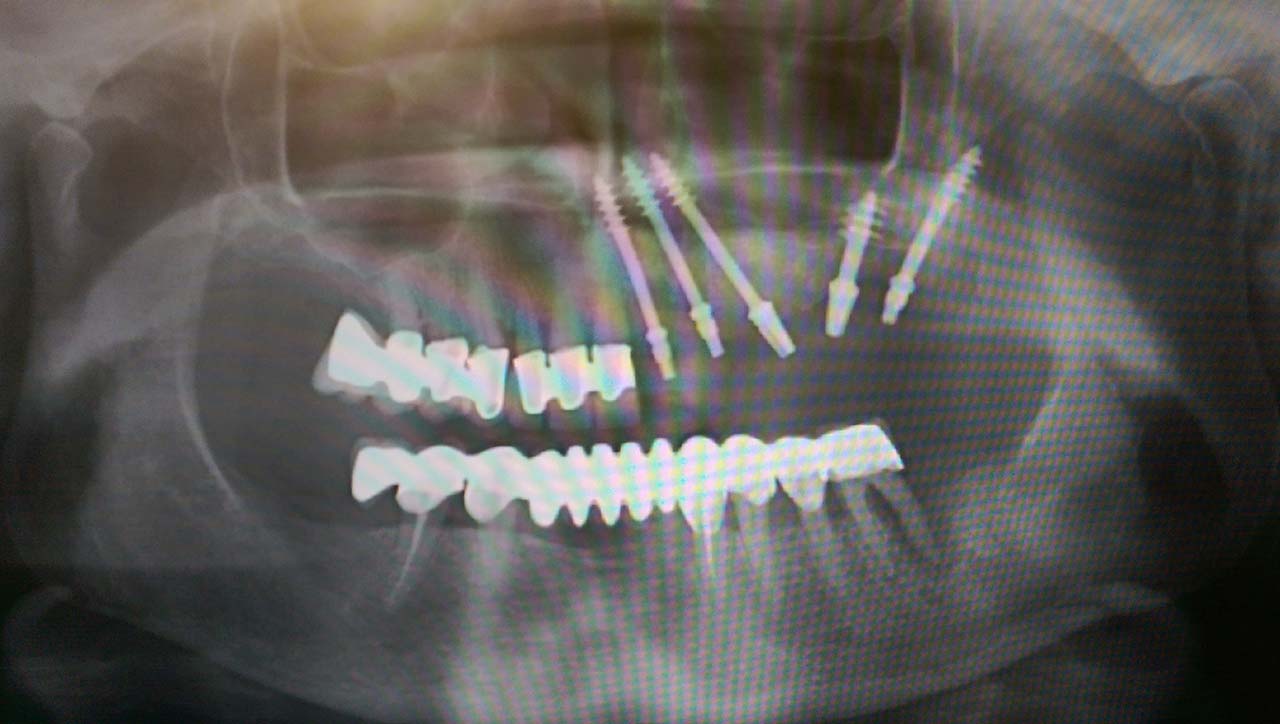

Alsó állcsont teljes rehabilitációja 72 óra alatt

Alsó állcsont teljes rehabilitációja 72 óra alatt, azonnal terhelhető implantátumokkal súlyos paradontitisben szenvedő dohányzó páciens esetében. Az alsó állcsont fogai mind mozogtak az előrehaladott fogágypusztulás miatt.

A fogakat eltávolítottuk, a gyulladt, fertőzött csontot kitakarítottuk, kifertőtlenítettük, majd azonnal implantáltunk.

Svájci, IHDE márkájú, azonnal terhelhető implantátumokat helyzetünk be, és ezekre harmadnapra rögzített, hosszútávú, fémvázas, esztétikus műanyaggal leplezett hidat ragasztottunk be.

Ezt az ideiglenes hidat a sebek gyógyulása miatt használjuk, de tartóssága miatt véglegesként is használható. A legtöbb esetben, ahogy itt is, 6 hónap múlva porcelán hídra cseréljük, a teljes gyógyulás után.